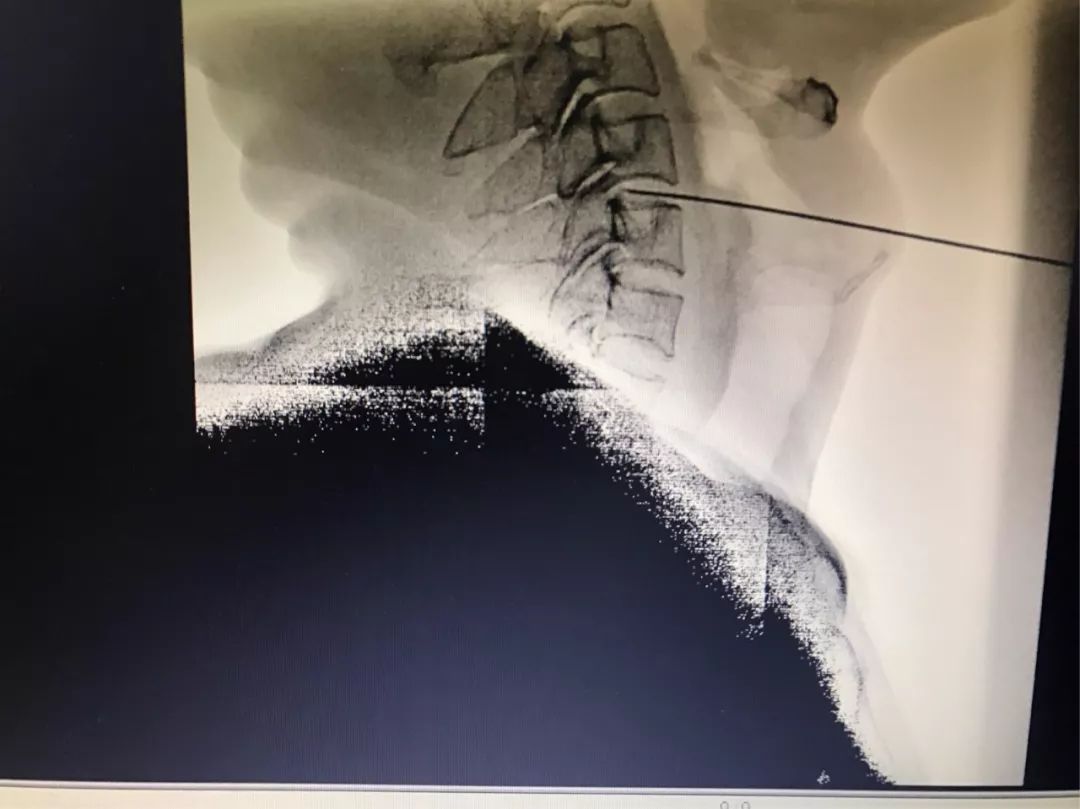

治疗过程是在C型臂引导下精确定位,在数字减影下进行检测,直接作用在病变的椎间盘上。数据精确到1mm以下,全程操作可视,不会伤及周围正常的组织器官及神经,射频温度可控,确保了治疗前后的安全,不感染,不存在热损伤。

穿刺针仅有0.7毫米(和输液针头一样细),不开刀,无出血,术后不影响脊柱的稳定性,危险小,恢复快。

射频所独具的安全测试系统能测到治疗范围1cm内的神经;独具阻抗显示功能,能分辨出髓核纤维环、钙化点,骨质和血管。能准确计算出要去掉的体积,不伤及正常组织,靶点直接定位突出部位,精确消融突出物,解除神经根压迫或刺激,快速缓解疼痛症状,重塑纤维环,一步到位治疗腰椎间盘突出症、脊髓型颈椎病。